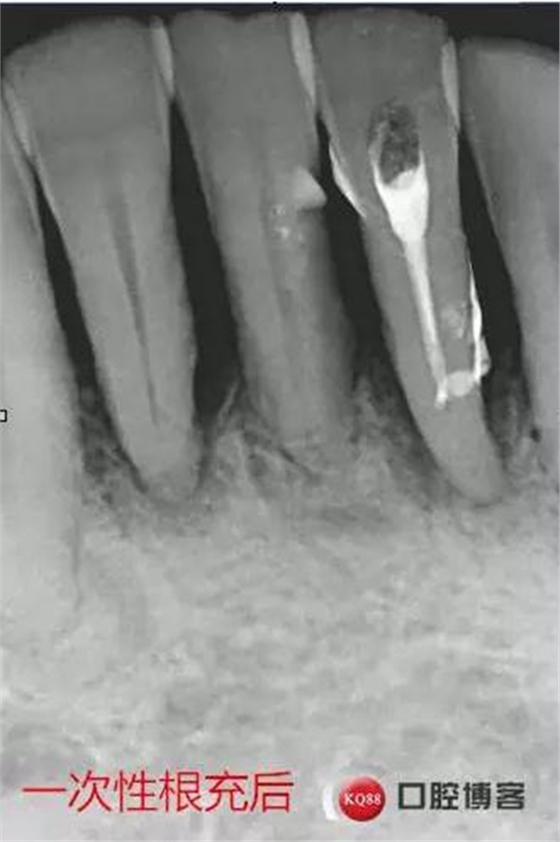

處理:上橡皮障,31開髓,測(cè)工作長(zhǎng)度17mm,含氯沖洗液沖洗,機(jī)擴(kuò)至04錐度30#,超聲蕩洗,一次性根充。33-43牙齒鄰接處super bond粘結(jié)固位,行松牙固定。調(diào)合。拍根充術(shù)后片,未達(dá)根尖,懷疑遺漏根管,去除根充物后,繼續(xù)探查根管,找到舌側(cè)根管,測(cè)長(zhǎng)度20mm,時(shí)間原因,未行擴(kuò)根,氫氧化鈣暫封。